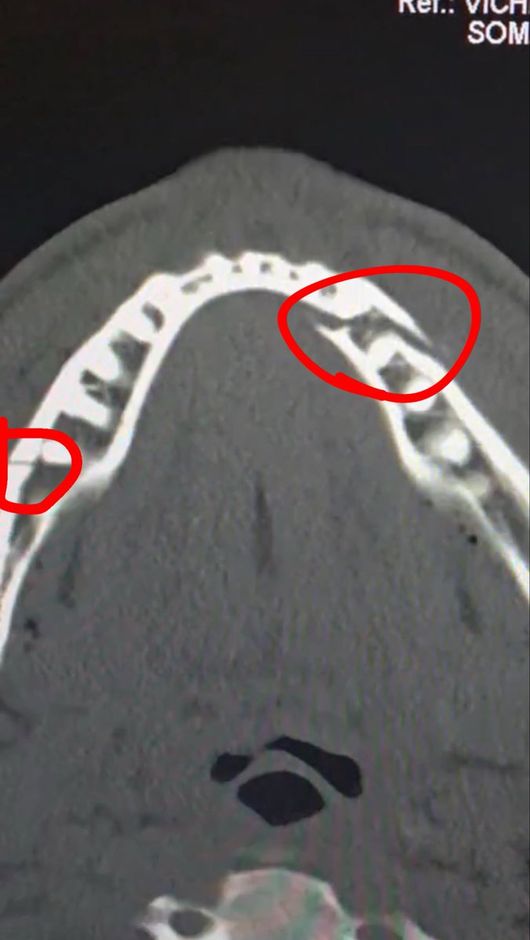

진단 결과 폴의 턱뼈는 두 곳이나 골절돼 세 동강이 난 모습이었다. 그는 곧바로 수술대에 올랐고, 티타늄 플레이트 두 개를 삽입했다. 치아도 일부 제거해 한동안 정상적인 식사도 불가능한 것으로 알려졌다.

폴은 소셜 미디어를 통해 자신의 수술 후 상태를 공개하면서 "통증이 심하지만 난 괜찮다. 턱뼈가 두 군데나 으스러졌다. 7일 동안 유동식을 먹어야 한다"라고 밝혔다. 경기를 앞두고 조슈아에게 "널 죽여버리겠다"라고 도발했던 폴이지만, 조슈아의 벽은 너무나 높았다.